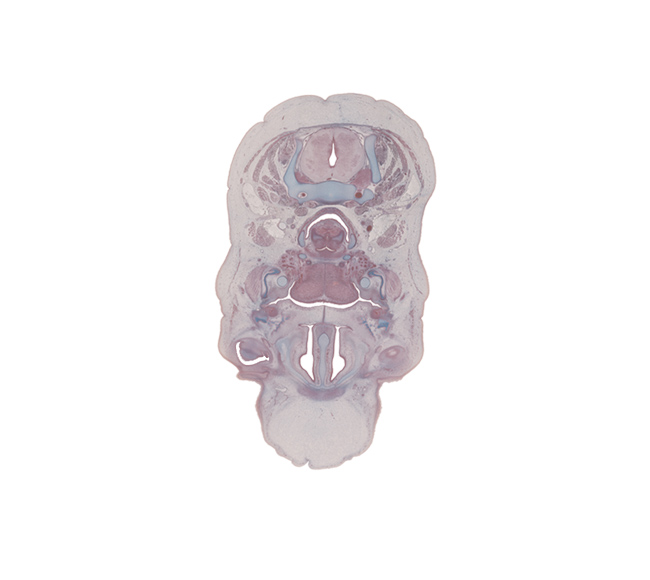

C-5 spinal ganglion, body of tongue, common carotid artery, conjunctival sac, edge of eyeball, fusion region of palatine shelves, greater horn of hyoid (pharyngeal arch 3 cartilage), internal jugular vein, interorbital ligament, jugular lymph sac, lesser horn of hyoid (pharyngeal arch 2 cartilage), linguogingival sulcus, lymph sac, masseter muscle, middle pharyngeal constrictor muscle, parotid duct, platysma muscle, retropharyngeal space, sternocleidomastoid muscle, sympathetic trunk, vagus nerve (CN X)

Carnegie Embryo #9226   |   Location: 77-01-01

Keywords: C-5 spinal ganglion, body of tongue, common carotid artery, conjunctival sac, edge of eyeball, fusion region of palatine shelves, greater horn of hyoid (pharyngeal arch 3 cartilage), internal jugular vein, interorbital ligament, jugular lymph sac, lesser horn of hyoid (pharyngeal arch 2 cartilage), linguogingival sulcus, lymph sac, masseter muscle, middle pharyngeal constrictor muscle, parotid duct, platysma muscle, retropharyngeal space, sternocleidomastoid muscle, sympathetic trunk, vagus nerve (CN X)